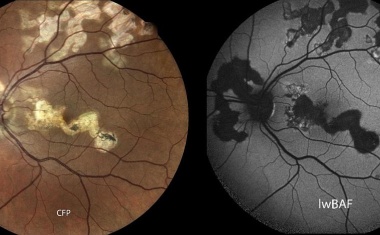

In einer internationalen klinischen Studie konnte bei Patient*innen mit geographischer Atrophie – einer schweren Spätform der altersabhängigen Makuladegeneration (AMD) – erstmals das zentrale Sehvermögen teilweise wiederhergestellt werden.

Uveitis-Experten aus Bonn, Berlin, Münster und Mannheim geben Überblick zu einer unterschätzten Bildgebung.